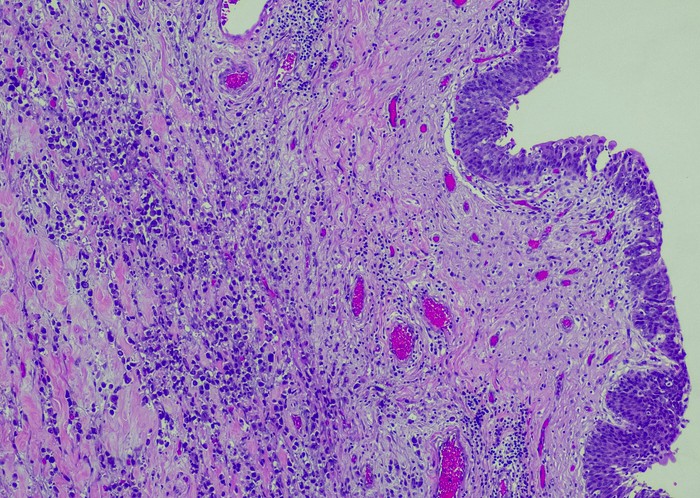

Featured photo at top of urothelial carcinoma cells stained purple. Photo/OGPhoto/iStock.

The research, published in the journal Urologic Oncology, focused on metastatic urothelial carcinoma (mUC), cancer that begins in the urothelial cells, which line the urethra, bladder, ureters and some other organs. Martini, University of Cincinnati Cancer Center physician-researcher and assistant professor in the Department of Urology in UC's College of Medicine, served as corresponding author of the study.